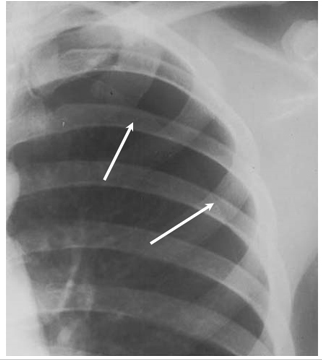

气胸x线x光

气胸x线x光,

气胸pneumothorax

气胸x线表现图片